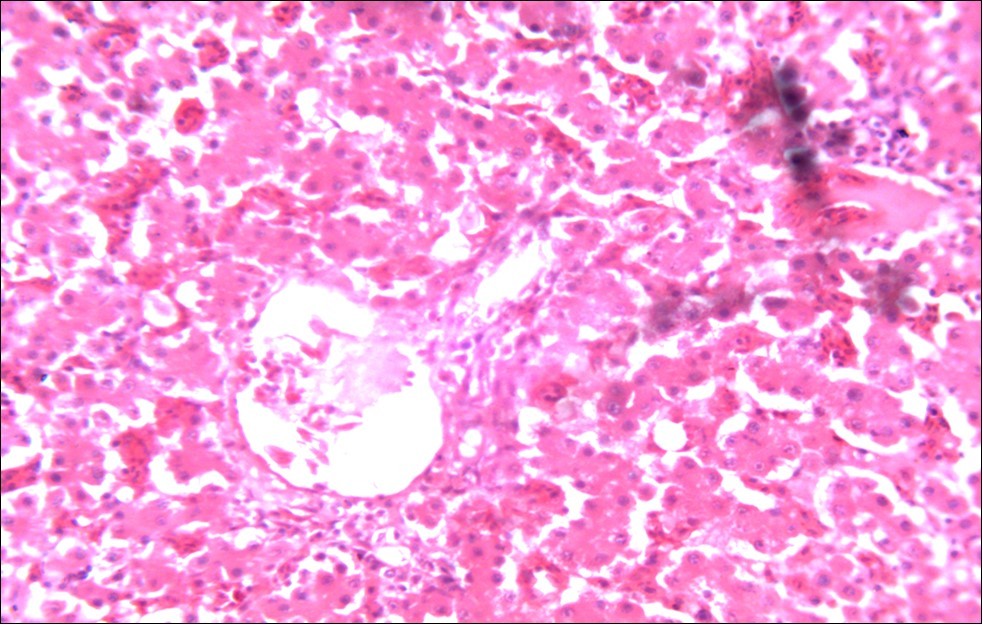

Figure 6.Photomicrograph of liver of chick administered NeemAzal® at 200 mg/kg showing no observable lesion X250 (H & E)

In addition, the generalized degeneration of the caecal glands, moderate numbers of gametocytes within the glandular regions with fibrosis which underscores reparative process in response to injury evoked by coccidiosis in the chicks which was perhaps brought about by the antioxidant and chemotherapeutic effect of NeemAzal®. The observed increase in RBC and hemoglobin concentration (Table 1) is indicative of the erythropoieticability of NeemAzal®, which is beneficial since the Eimeria parasite in the epithelia of the intestines causes bloody diarrhea and consequently anaemia. This finding is in consonance with 15 who reported an anti-anaemic effect of Khaya senegalensis on phenyl hydrazine-induced anaemia in rats. If the results of this study are juxtaposed with the results of the previous studies on potent antioxidant, hepatoprotective and mitigative role of methanolic extracts of Azadirachtaindica,in both natural and experimental infection with Eimeria species and can be deduced that, NeemAzal® could be said to be a potent antioxidant, chemotherapeutic and tissue protective agent. This study also answered a question on further study advocated to determine the maximum safe levels of neem supplementation because the higher doses, due to its bitterness, may show adverse effects on feed intake which will change the performance parameters of birds (Figure 6 and Figure 7) . Light microscopic inspection of hematoxylin and eosin-stained sections revealed that the epithelial cells of the Cecum were infected by E. tenella(Figure 3 and Figure 4). The results of the safety study showed that exposure of chickens to NeemAzal® at 200mg/kg body weight did not alter the histoarchitecture of liver and kidney (Figure 6 & Figure 7) which is similar to the work conducted in the same environment by a group of Scientists 34. It is therefore recommended that NeemAzal® could be used as a coccidiostat to replace the expensive anti-coccidiostats in the market.